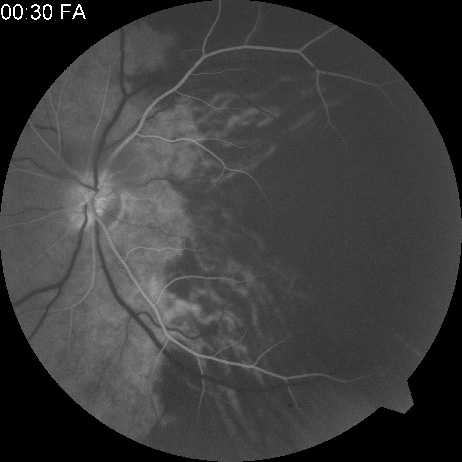

Fig. 3. A: Cilioretinal artery obstruction showing opacity of the retina in the area of obstruction. B: The cilioretinal artery has begun to fill after the branches of the central retinal artery but is still not completely filled at this point in the angiogram.